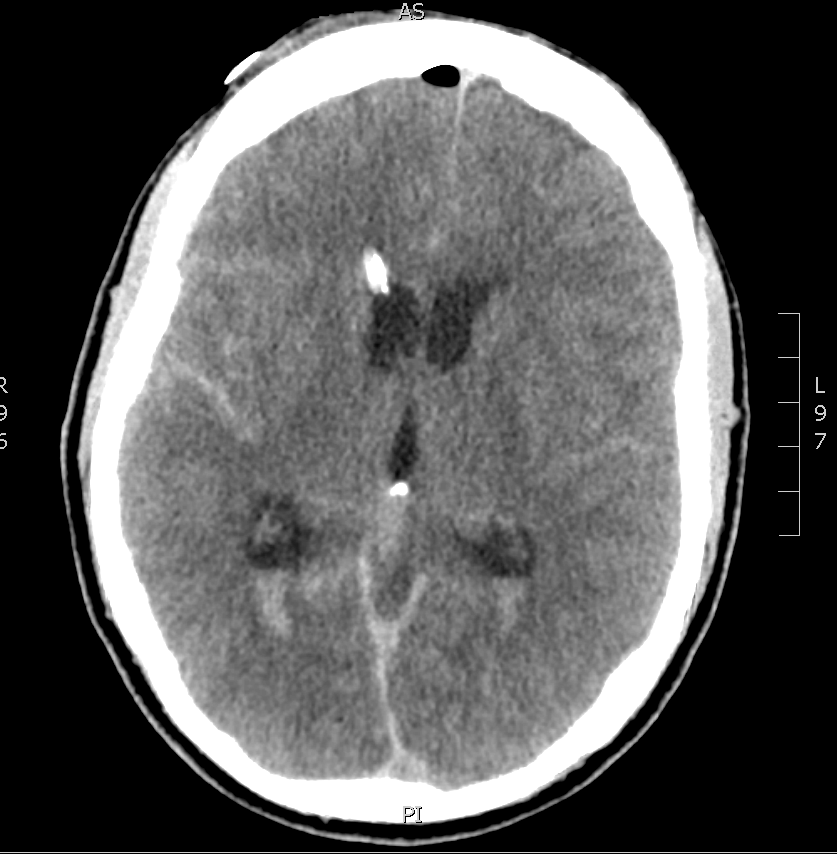

A few pointers from a single illustrative head CT.

Lets take a look at the head CT from a single patient, admitted to the neuro ICU three days ago. Can you guess from the image what the admitting diagnosis is?

There is a lot going on in this CT – but you may have realized that there is diffuse subarachnoid hemorrhage. There are a number of other findings that we’ll walk through. First, take a look at using our coronal and sagittal views – fun fact, these are simply computer reformats of the axial above.

Now, let’s get into the specifics of the axial image. Scroll down for the key.

The highlighted structures are:

- Red Arrow – subarachnoid blood; you know it’s blood because it’s hyperdense, and it’s subarachnoid because it’s settled inside the cerebral gyri.

- Green Arrows – this is intraventricular blood, layering out in the bottoms of the lateral ventricles due to gravity (in this case, the source is the subarachnoid blood).

- Yellow Arrow – a tricky one, this is a ventricular drain, or EVD – commonly used to prevent the development of hydrocephalus after subarachnoid hemorrhage. Look for it again in the coronal and sagittal images above.

- Blue Arrow – Free air, given how hypodense it is, and it has found its way to the top of the cranium, as you would expect an air bubble to do. The source if the EVD.

- Orange Arrow – The third ventricle

- Pink Arrow – Dural venous sinus